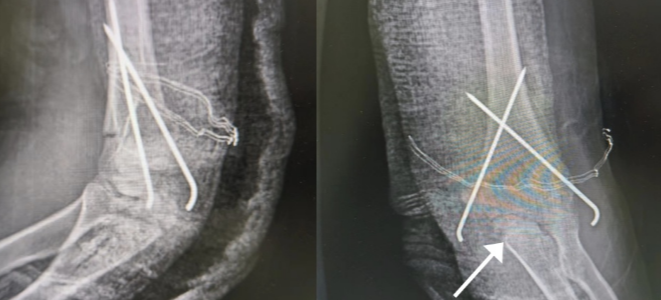

图片

(受访者供图:术后复查X线,骨折复位良好)

胡海澜介绍,肱骨髁上骨折是儿童最常见的骨折之一,如果不能良好地复位和固定,日后将遗留肘关节内外翻畸形甚至出现迟发性尺神经炎。左肱骨髁上骨折的俊俊,行闭合复位克氏针内固定,术口仅为2个3mm针眼大小伤口,小小的创口解决了骨折大问题。